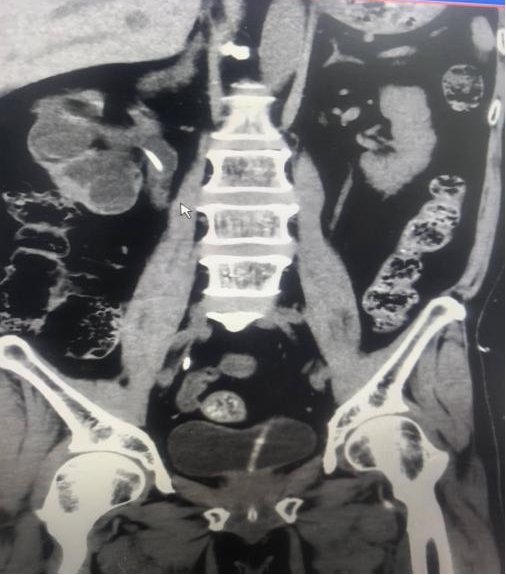

我科近期收治一名中年男性患者,因右肾下盏结石反复引发炎症导致腰痛,就诊后表达了对微创治疗的需求。

术前↑

经科室医护团队综合评估其病情、身体条件后,为其制定了输尿管软镜治疗方案,目前患者已顺利完成治疗,恢复良好。(本案例经患者同意作为宣传)